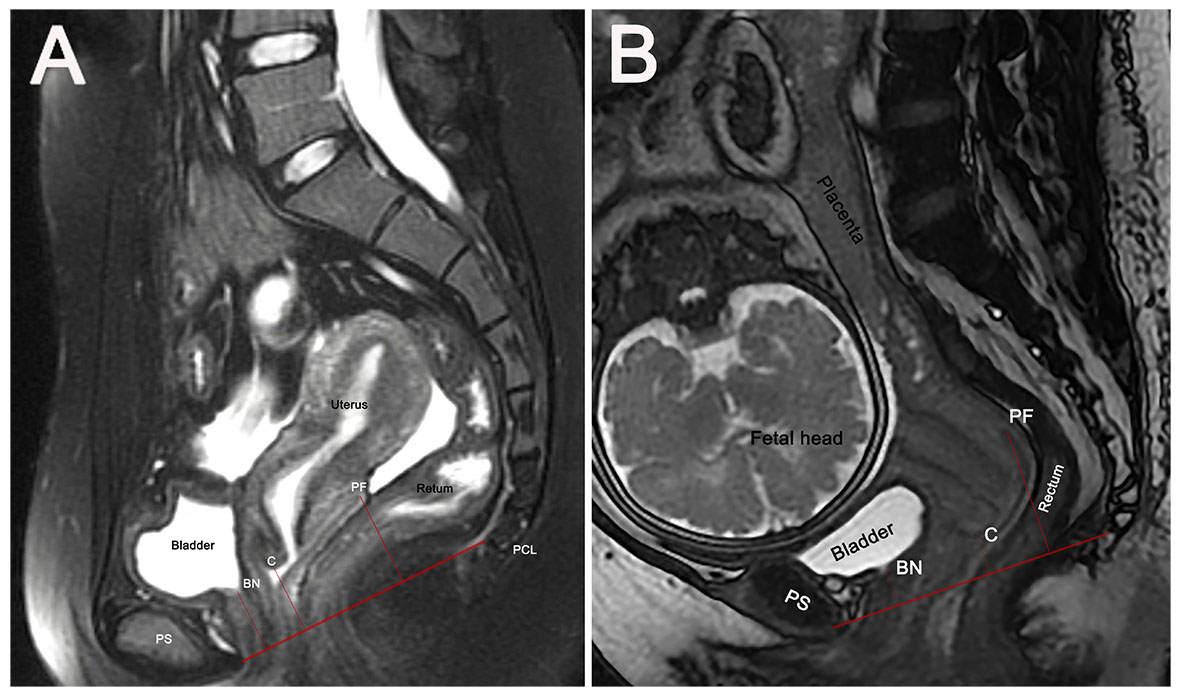

The pubococcygeal line (PCL), the recommended MRI reference line for diagnosing POP, extends from the pubic symphysis’s inferior aspect to the last coccygeal joint [19]. Perpendicular distances from the PCL to the bladder neck (BN), the cervix’s most distal edge (C), and the posterior fornix’s apex (PF) were measured (Fig. 1). Organ-specific reference points above the PCL had positive values (+), while those below had negative values (–).

Fig. 1. Sagittal MRI-based measurement of pelvic organ positions relative to the pubococcygeal line (PCL). PCL is the red line from pubic symphysis to the last coccygeal joint. Perpendicular distances from the PCL to anatomical points BN, C, and PF are measured (denoted by short red lines) in non-pregnant women (A) and pregnant women with cephalic presentation (B). BN, bladder neck; C, most distal cervical edge; MRI, magnetic resonance imaging; PF, apex of the posterior fornix; PS, pubic symphysis.